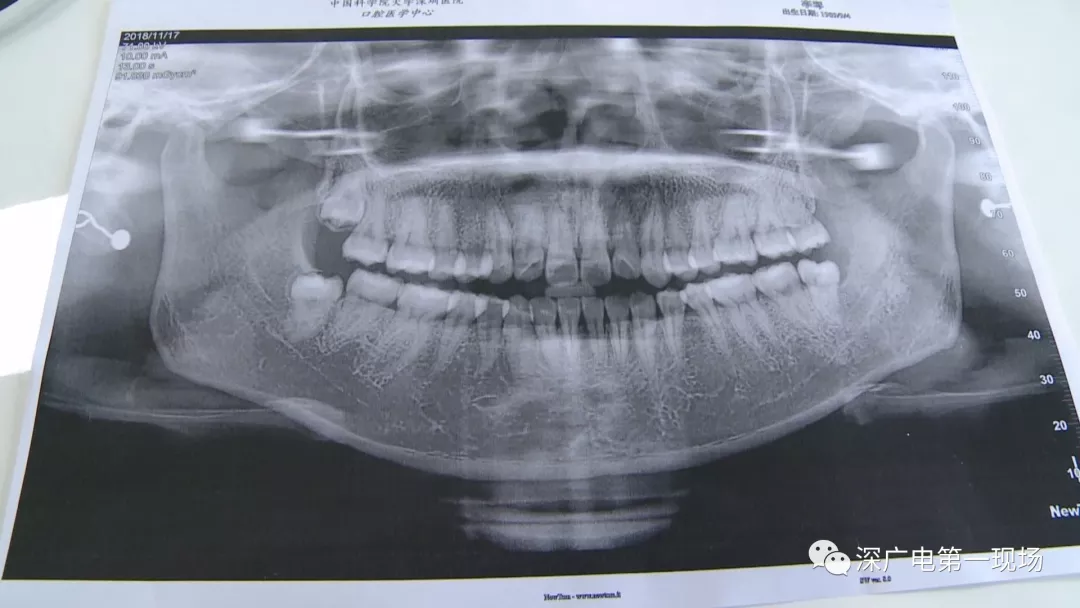

針對李女士的情況,醫(yī)生介紹,當(dāng)時要想拔出李女士的這顆智齒,難度還是很大的,屬于復(fù)雜智齒的拔除術(shù)。她的風(fēng)險(xiǎn)在于距離神經(jīng)管近,同時這顆牙齒完全埋在牙床最后的位置,直接往外拔,會加大頜骨的風(fēng)險(xiǎn),因此需要先切開,讓牙齒暴露后,切小再慢慢地拔出。